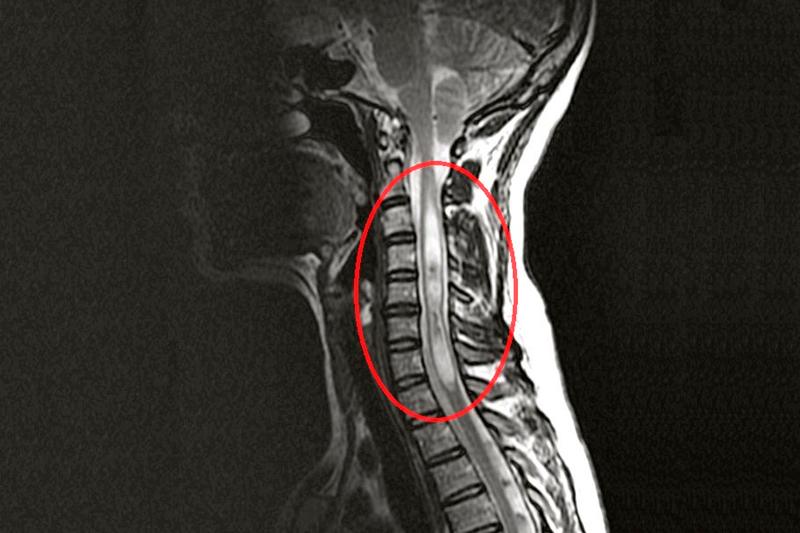

CLINICADebutul clinic al hemoragiei medulare apare de obicei brusc. Se manifestă clinic printr-o durere de intensitate mare în membrele superioare, dupa care se instalează o paralizie a tuturor membrelor, deoarece hemoragia se produce adeseori la nivelul umflăturii cervicale. Examenul neurologic mai pune în evidență, și abolirea reflexelor osteotendinoase. Se întâlnesc și tulburări ale sensibilității termice și dureroase. Deoarece sângerarea se întinde și la nivelul coarnelor anterioare, apar semne de atrofie a musculaturii membrelor superioare și tulburări respiratorii. Se poate întâlni, și un sindrom Horner, care se manifestă prin mioză, ptoză palpebrală, diminuarea sudorației la nivelul hemifaciesului ochiului afectat. Dupa ce starea de șoc este depășită, în următoarele zile când măduva scapă de sub influența inhibitorie a scoarței cerebrale, se obiectivează exagerarea reflexelor osteotendinoase. În cazul hemoragiei în spațiul dural sau epidural, sângele care se acumulează are ca efect comprimarea măduvei sau rădăcinilor radiculare. DIAGNOSTICIRM (imagistica prin rezonanță magnetică) este metoda cea mai indicată pentru stabilirea diagnosticului. În cazul în care se suspectează o malformație vasculară ca fiind cauza hemoragiei, se efectuează o angiografie selectivă spinală. TRATAMENTTerapia este în general suportivă. Dacă hemoragia este rezultatul unei malformații vasculare, atunci se intervine chirurgical în urgență pentru evacuarea cheagului și pentru a rezolva leziunea vasculară cauzatoare. În cazul hemoragiei subarhanoidiene care comprimă măduva, se intervine chirurgical pentru decompresie.